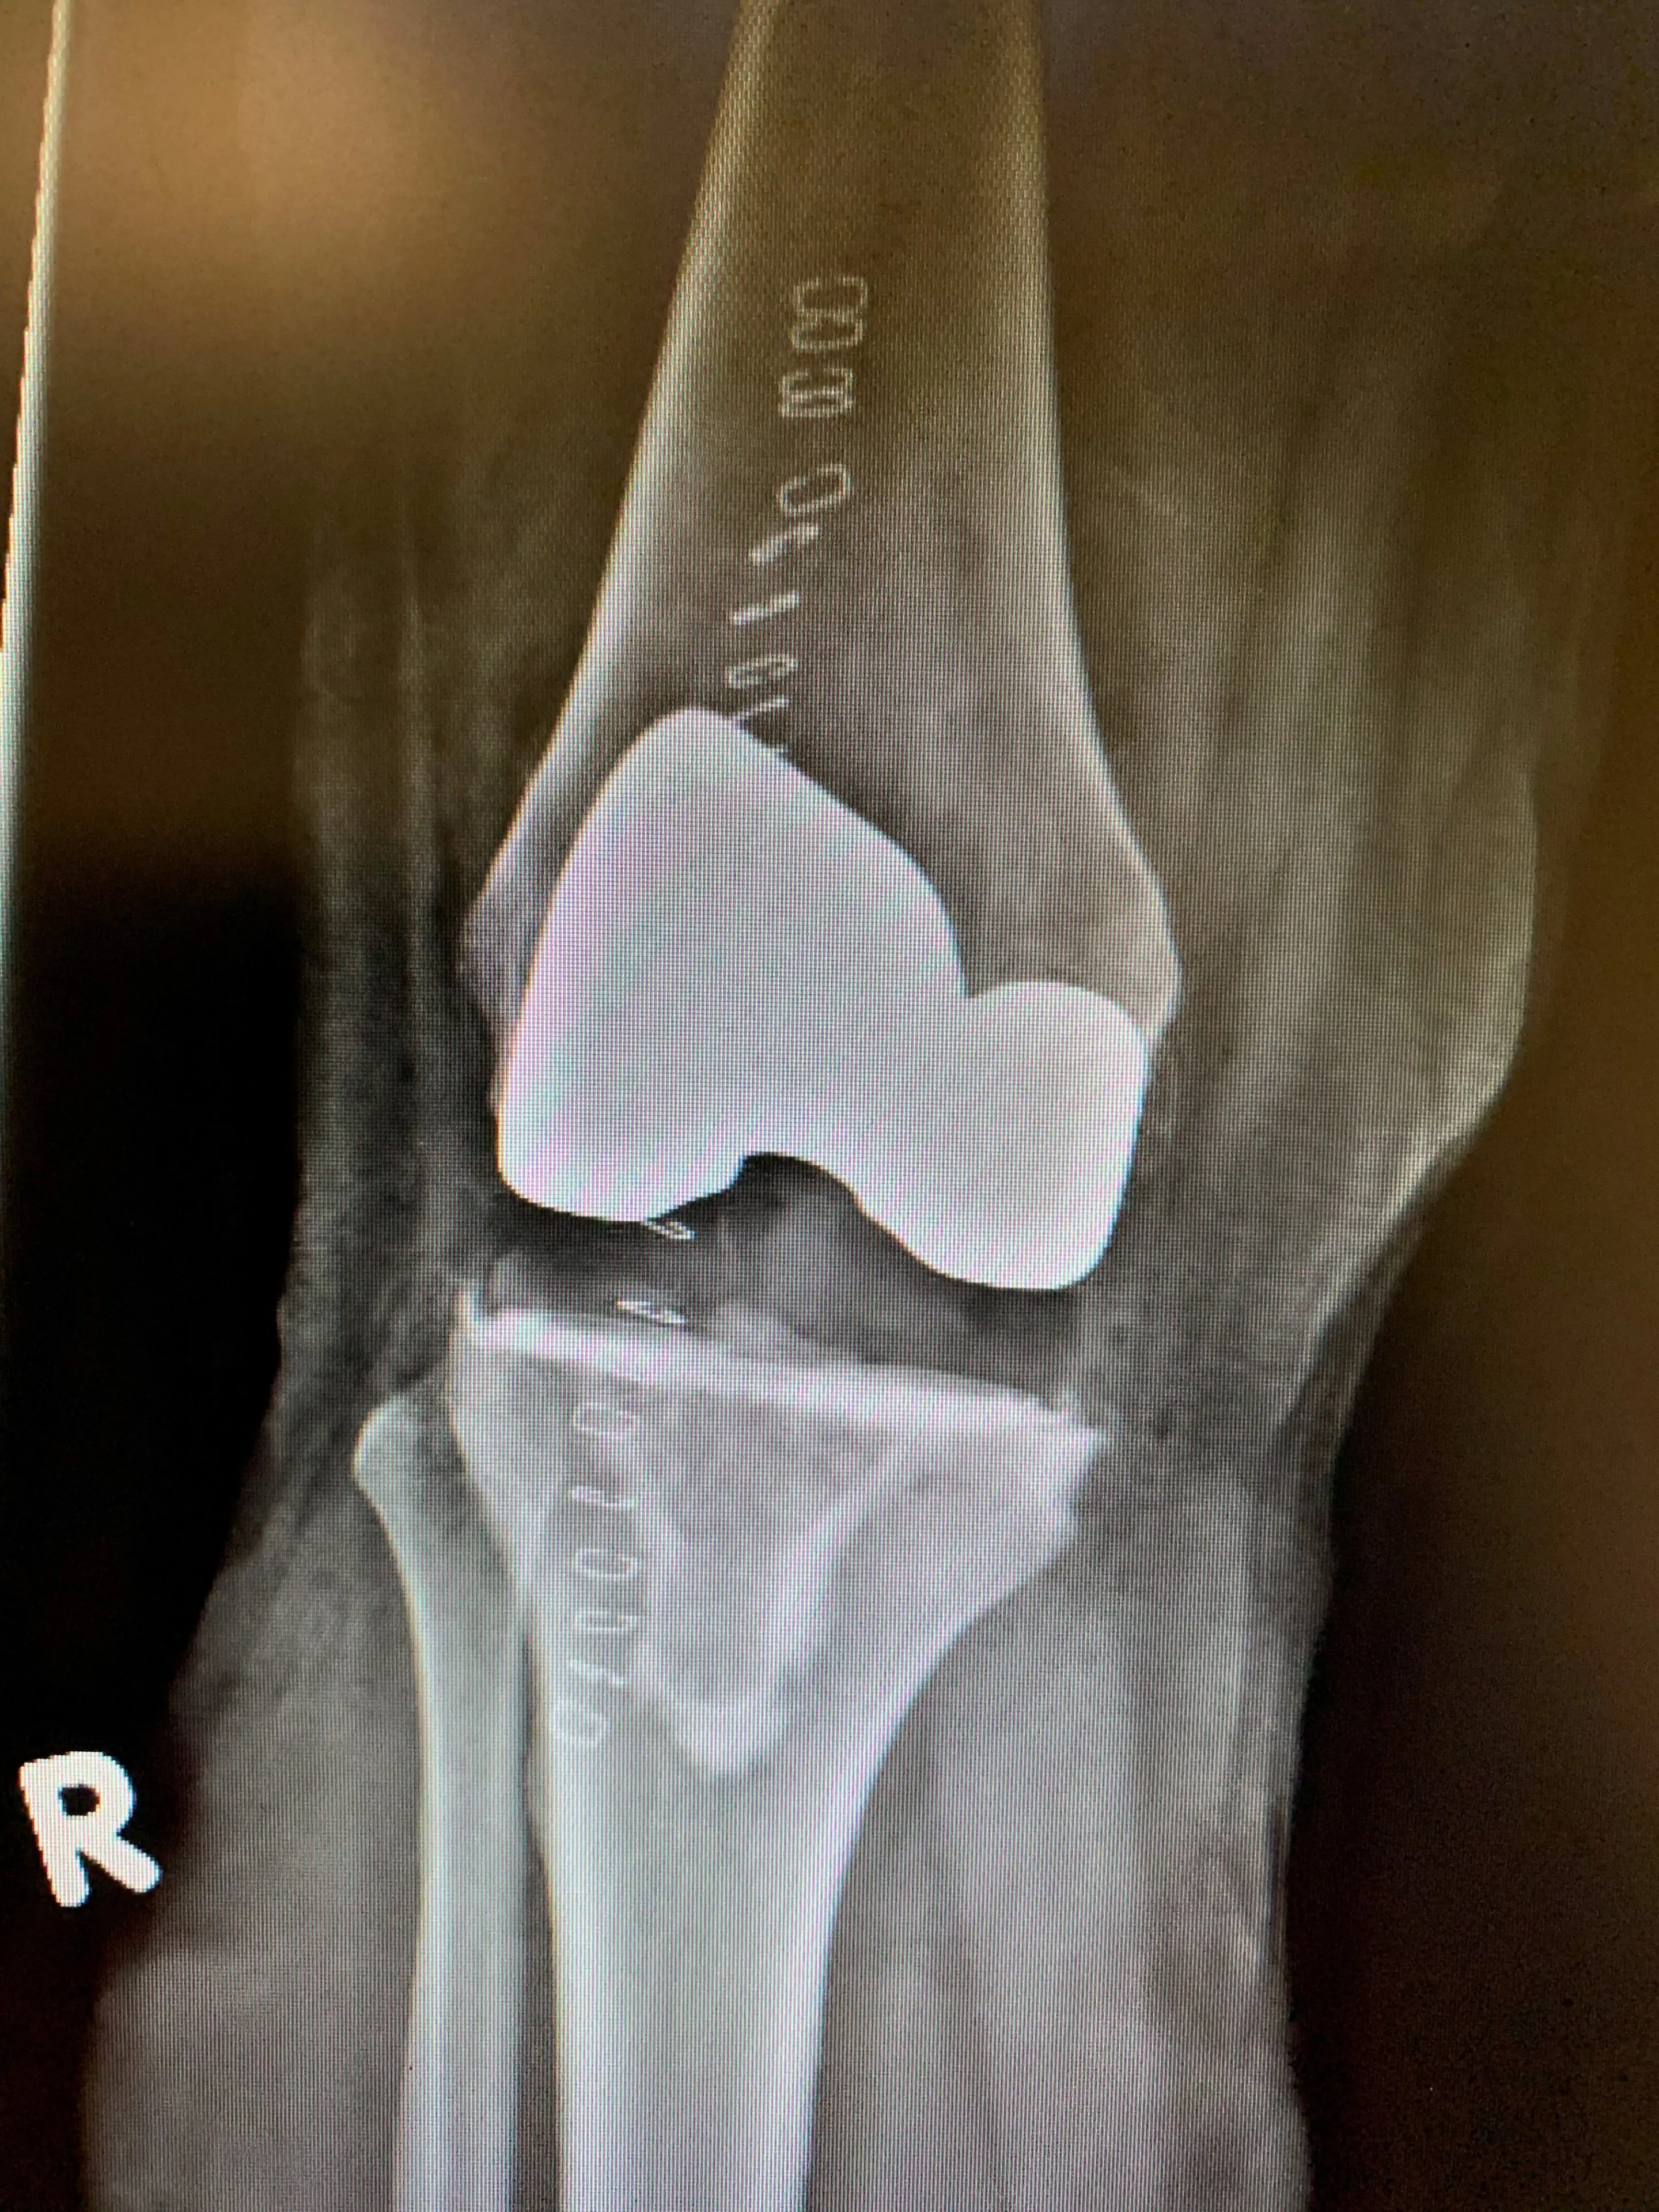

Post-opComputer navigated Primary Knee replacementb

Computer navigated primary knee-replacement